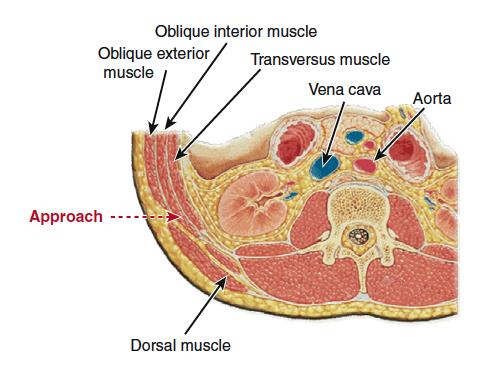

A nivel lumbar también se ha desarrollado la técnica de XLIF (de abordaje lateral directo) que tiene la particularidad de salvaguardar y preservar estructuras anatómicas (Fig 1).

Se realiza disección roma, separación de las estructuras con torundas, y especial cuidado, para evitar lesionar estructuras.

Se deja el peritoneo por delante de la columna vertebral. El psoas queda en la parte lateral de la columna, y hay que entrar entre sus fibras, intentado separarlo hacia posterior.